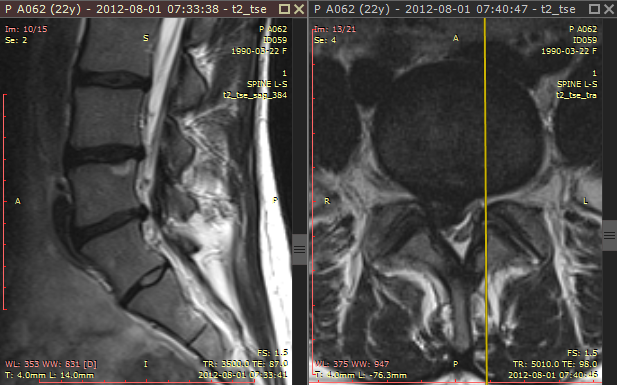

浏览不同图像平面的序列时(例如磁共振检查),交叉参考线可帮助更好地关联解剖结构。它们显示为黄色线条,标记各图像平面的交线位置。

交叉参考线示例 2

交叉参考线始终在非活动面板(灰色标题栏)中显示,作为活动面板(棕色标题栏)图像的参考。